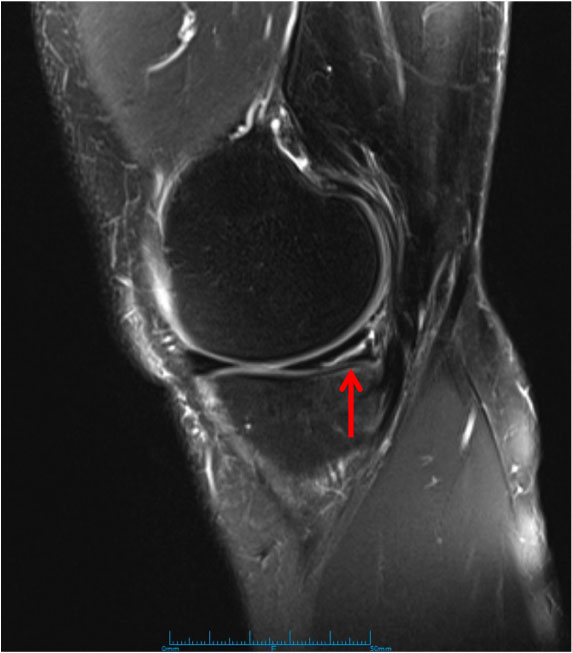

Expand your clinical knowledge with WikiSM.org —a comprehensive resource for sports medicine, MSK exams, and rehabilitation—and MedEdCases.com for real-world, case-based emergency medicine learning